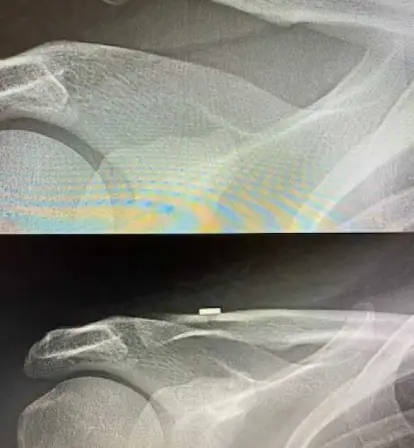

Joint replacement begins with careful evaluation and planning. Clinical examination and imaging help understand the extent of joint damage and determine the most suitable approach for each patient.

Planning focuses on accuracy and safety, ensuring the procedure supports smooth recovery and long-term joint function. This structured approach reflects the clinic’s commitment to reliable outcomes under Advanced Orthopedic Care.